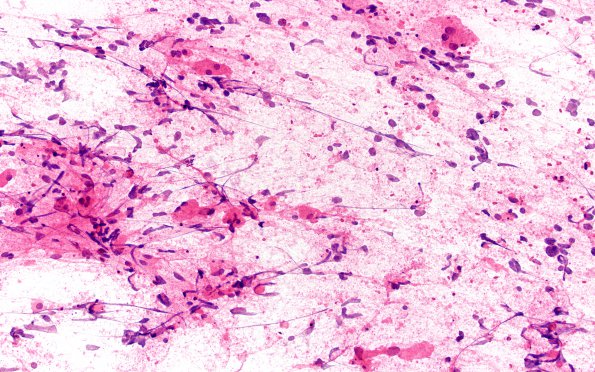

Glioblastoma, granular cell type

7B1 Glioblastoma, granular cell type (Case 7) TP 20X

An intraoperative smear shows numerous granular tumor cells. (H&E)